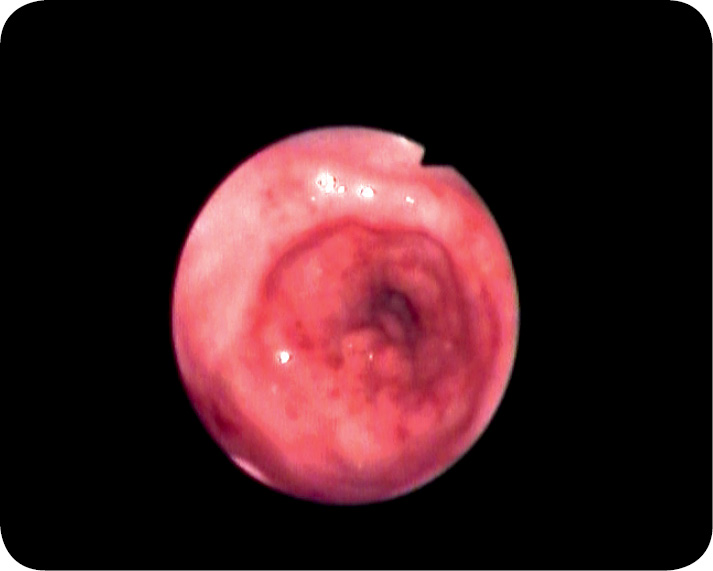

Podczas badania endoskopowego stwierdzono: błonę śluzową przełyku makroskopowo normotypową, zamknięty dolny zwieracz przełyku, obrzękniętą, zaczerwienioną, kruchą błonę śluzową trzonu i części odźwiernikowej żołądka z obecnymi nadżerkami i owrzodzeniami, utrudnione wprowadzenie endoskopu do części odźwiernikowej żołądka oraz brak możliwości obserwowania zwieracza odźwiernika, co było konsekwencją silnego zwężenia części odźwiernikowej żołądka (ryc. 1 i 2). Z części odźwiernikowej żołądka pobrano wycinki błony śluzowej do badania histopatologicznego.